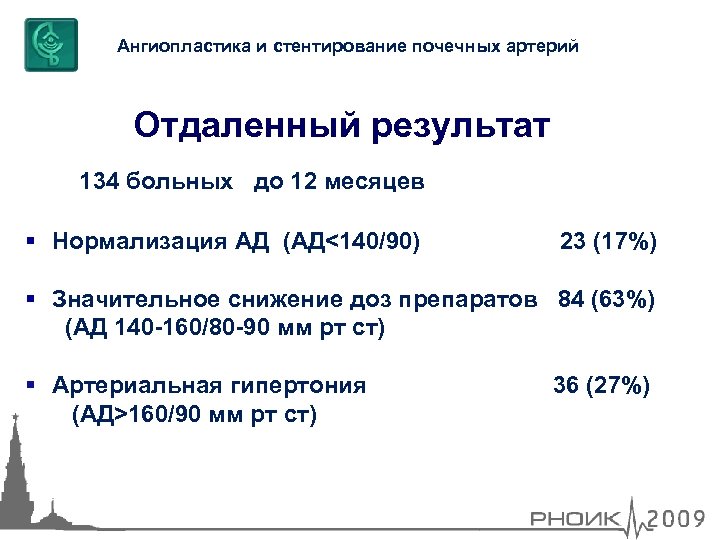

Ангиопластика и стентирование почечных артерий Отдаленный результат 134 больных до 12 месяцев Нормализация АД (АД<140/90) 23 (17%) Значительное снижение доз препаратов 84 (63%) (АД 140 -160/80 -90 мм рт ст) Артериальная гипертония (АД>160/90 мм рт ст) 36 (27%)

Ангиопластика и стентирование почечных артерий Отдаленный результат 134 больных до 12 месяцев Нормализация АД (АД<140/90) 23 (17%) Значительное снижение доз препаратов 84 (63%) (АД 140 -160/80 -90 мм рт ст) Артериальная гипертония (АД>160/90 мм рт ст) 36 (27%)